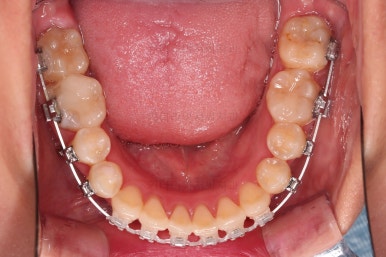

초진 시 입안의 모습입니다.

이미 썩어서 부러진 치아도 몇 개 보이고요.

많이 삐뚤어진 치아쪽은 양치가 힘들어 이미 많이 썩어 있는 상태에 덧니쪽은 잇몸도 많이 내려간 상태였습니다.

말그대로 교정치료 뿐만 아니라 전반적인 치료가 필요한 상황이었습니다.